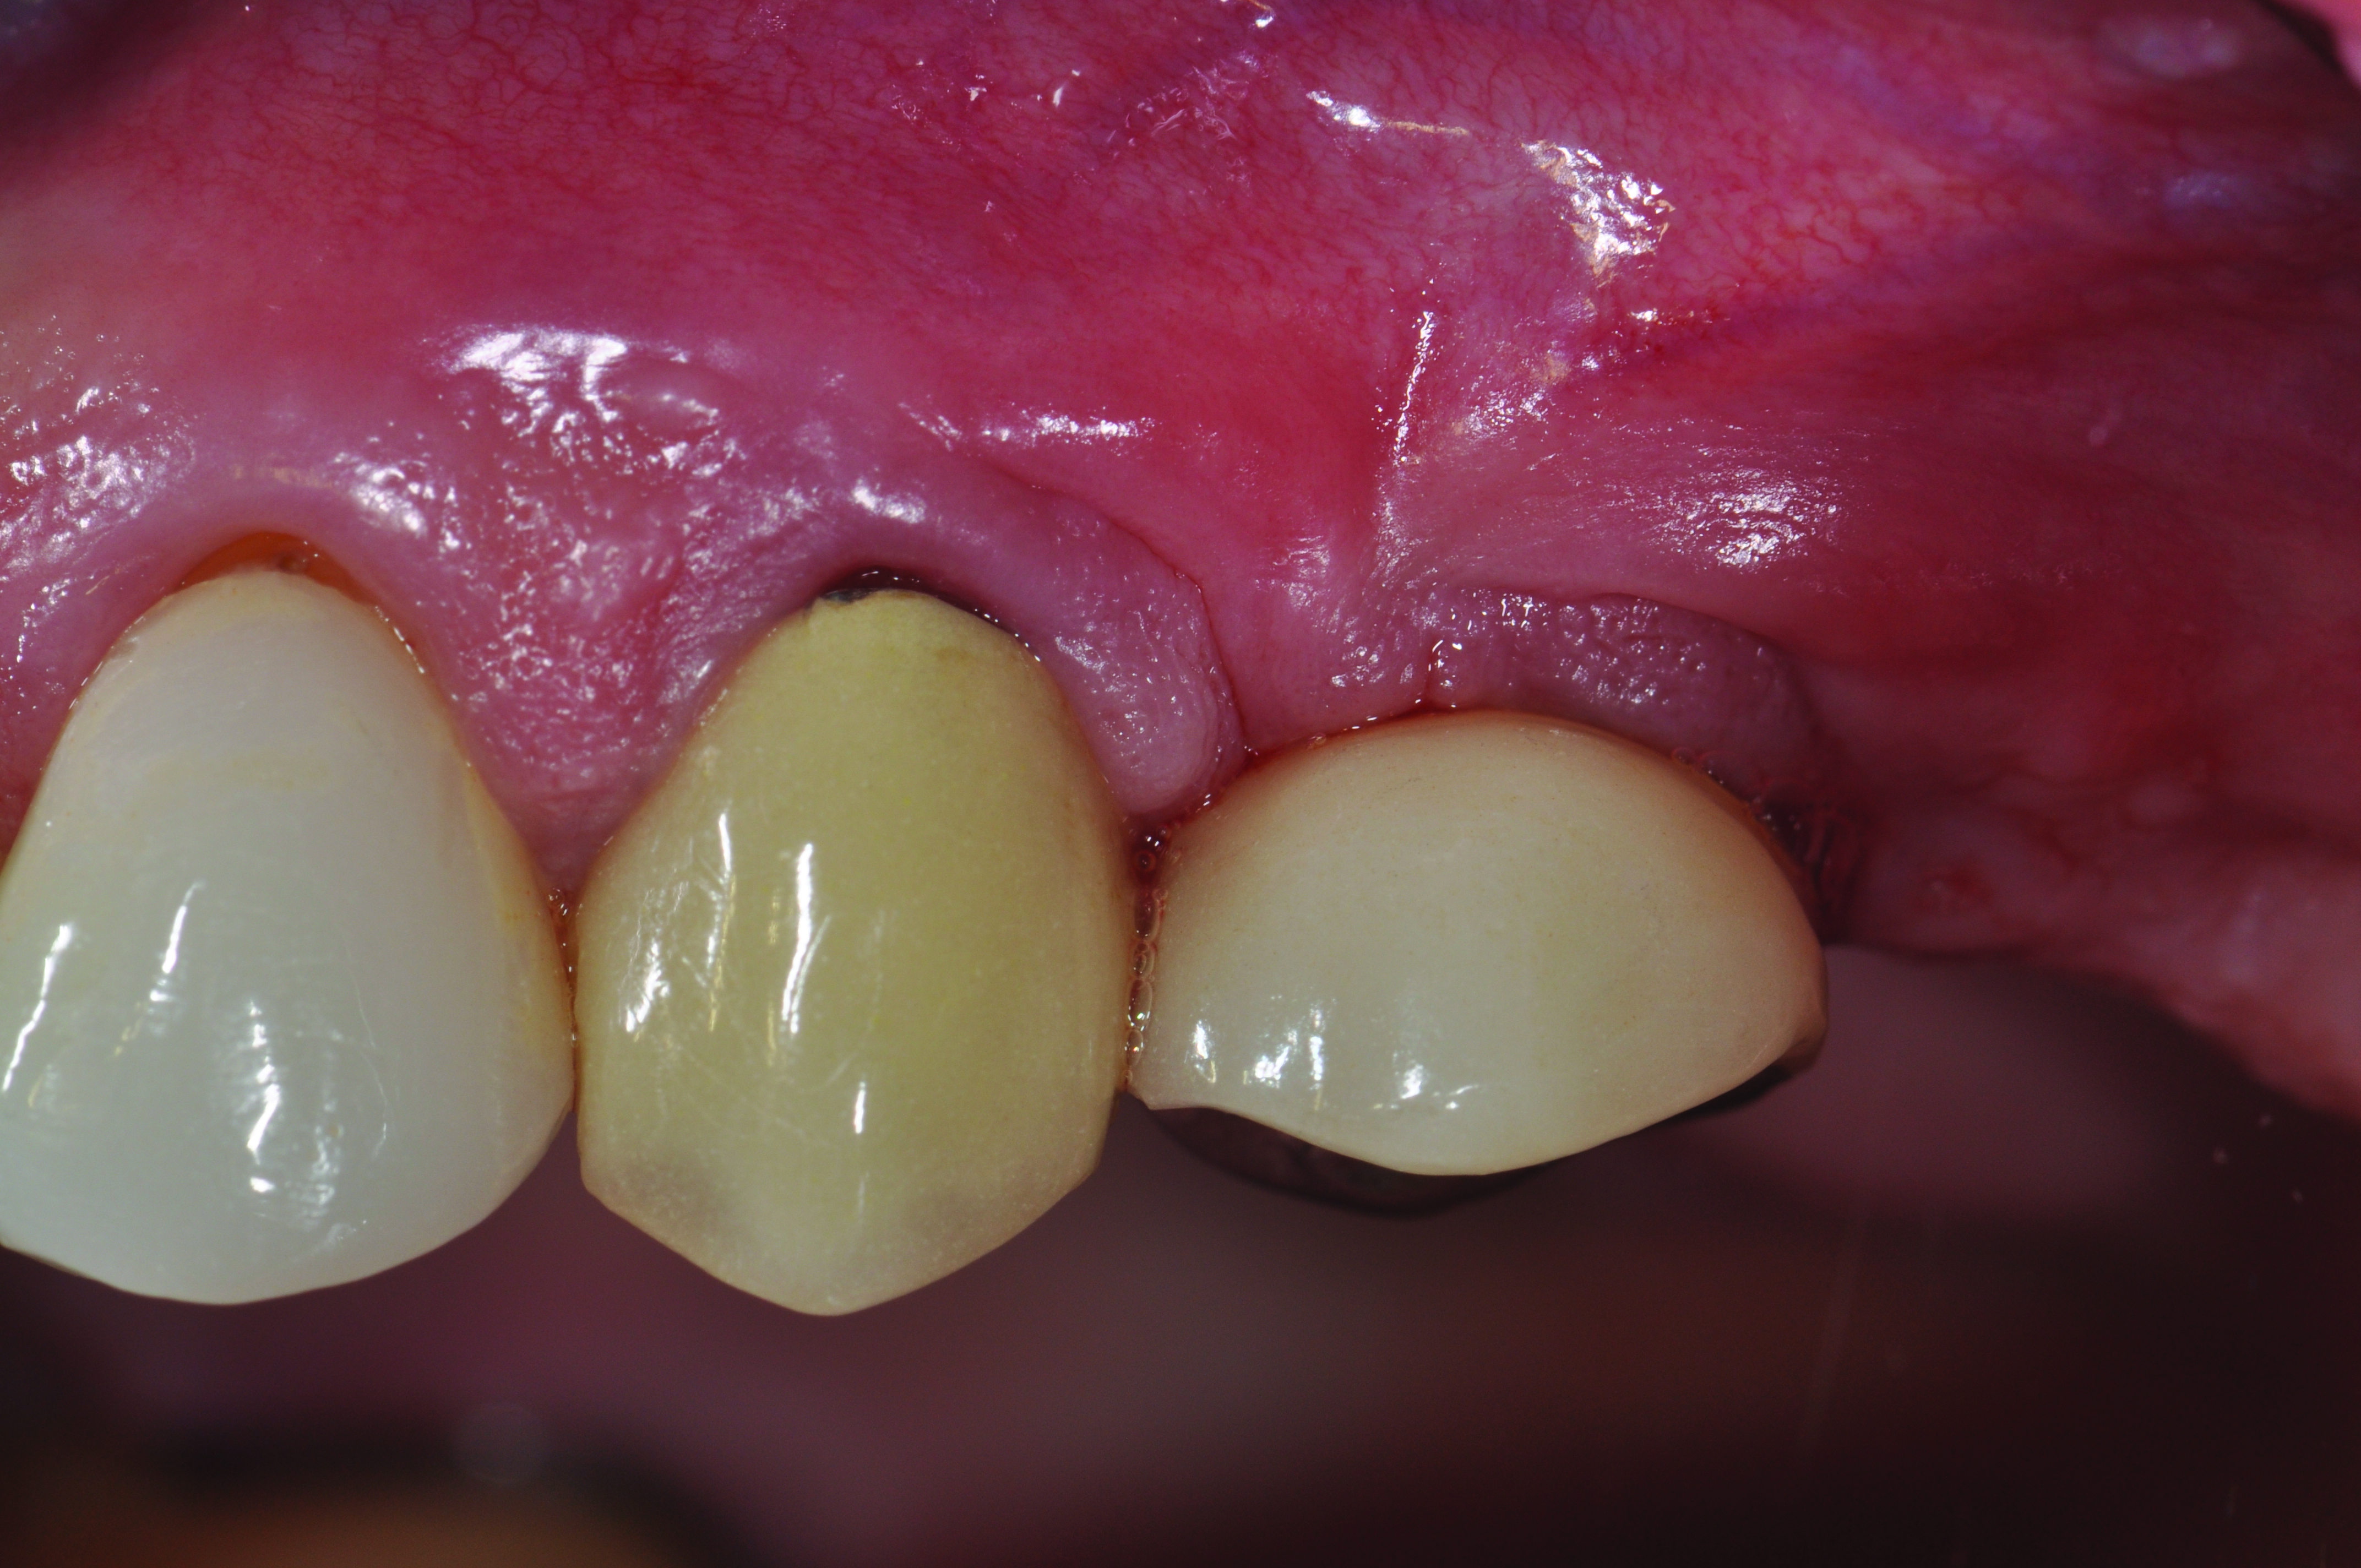

Clinical view of maxillary left lateral incisor implant in a healthy 48-year-old man. The swelling in the tissue surrounding this implant also bled on probing with depths up to 8 mm and exhibited purulence. The implant has been present for 14 years.

Figure 1

Radiograph of this same area. Note that there is no indication of bone loss and a long abutment collar. Hence, the diagnosis of peri-implant mucositis is given.

Figure 2